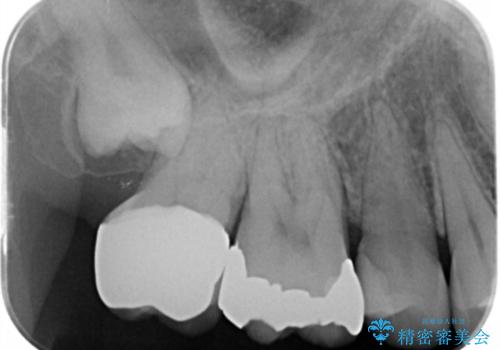

奥歯がしみて痛い

- 冷たいものがしみて飲み物が飲めないとの事で来院。

歯肉が退縮していたので歯周外科手術(歯茎の移植手術)か被せ物で覆う(歯肉退縮しているところまで覆う)の提案をしたところ被せ物がいいとのことでしたので

被せ物の治療のご案内になりました。

適合の良い被せ物が入りました。

冷たいものがしみなくなり大変満足してもらいました。

一つ前の歯も後に染みてくる可能性があるとの事で被せ物をするか検討中です。